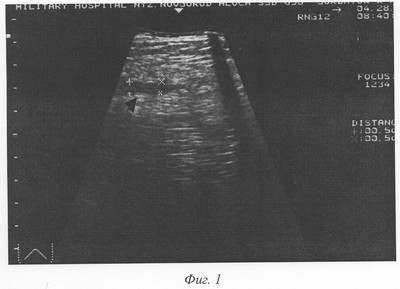

Фиг.1 – эхограмма передней брюшной стенки живота на 3-й день после аппендэктомии больного С., 20 лет. Определяется гипоэхогенная зона (обозначена крестами) на глубине апоневроза наружной косой мышцы живота толщиной 5 мм.

Пример 1. Больной С., 20 лет, история болезни №1941, поступил в клинику 22.03.2001 года с диагнозом «Острый аппендицит». Диагноз подтвержден данными анамнеза, объективного обследования и лабораторными показателями. Операция – аппендэктомия. Послеоперационный диагноз: катаральный аппендицит. Операционная рана ушита наглухо. В послеоперационном периоде боли в области раны купировались 24.03.01. Гиперемия в области швов исчезла на 4-е сутки. Средняя температура тела в первые 4 суток послеоперационного периода 37,3°С. При сканировании области послеоперационной раны, на глубине апоневроза на 3-й сутки (25.03.01) гипоэхогенная зона толщиной 5 мм (фиг.1). 27.03.01 г. гипоэхогенная зона в той же области уменьшилась до 3 мм, на 7-е сутки – толщина гипоэхогенной зоны – 3 мм (фиг.2). Швы на коже сняты на 7-й день после операции. Заживление раны первичным натяжением. Выписан в удовлетворительном состоянии.